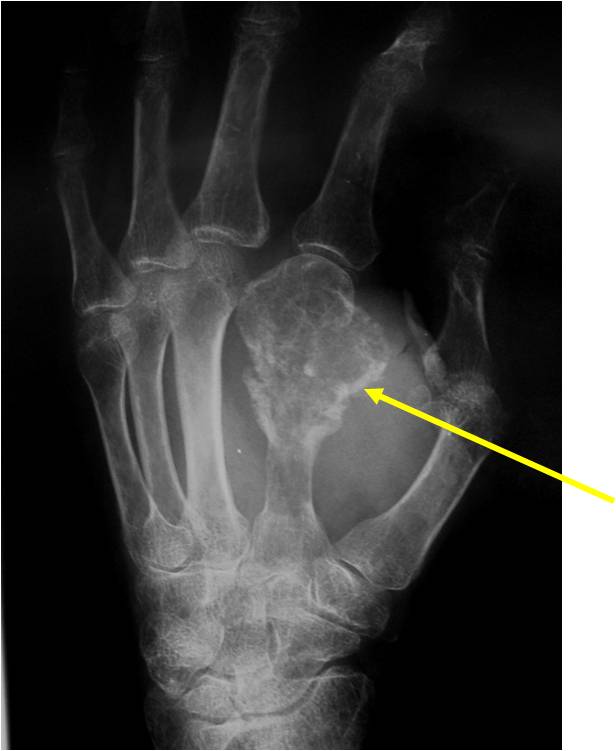

- Localized, radiolucent defect usually with punctate calcifications

- Calcifications are stippled, punctate, popcorn like calcifications and “Ring and Arc” calcifications

- Cartilage tumors grow in a lobular manner. The perimeters of the lobules undergo

- enchondral ossification that may calcify. If the entire perimeter of the lobule calcifies it appears

- radiographically as a “Ring”. If a portion of the perimeter of a lobule calcifies it forms an “Arc” on

- an X-ray.

Plain X-Ray:

- Geographic lytic lesion

- Central often metaphyseal in long bones

- Expansile remodeling with thinned cortex

- Chondroid matrix with calcifications in majority of tumors